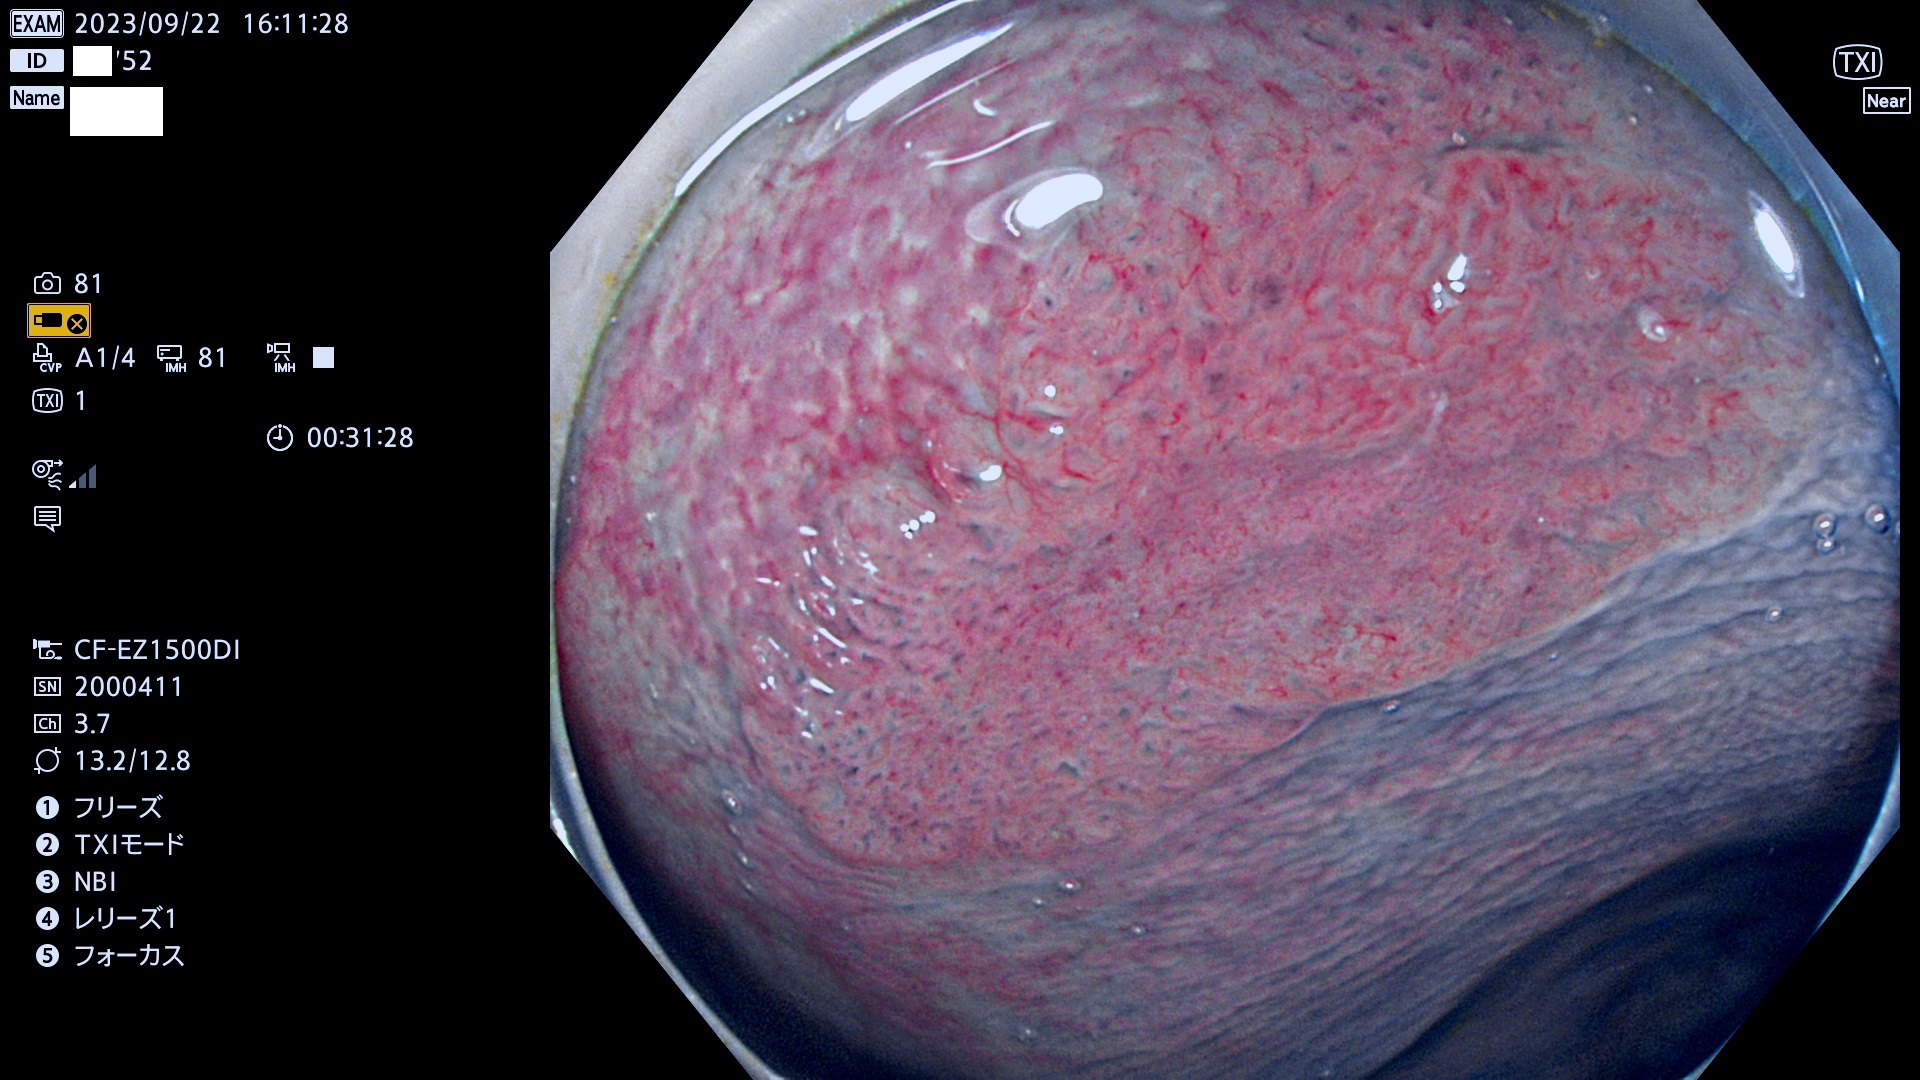

表面型腺腫(Flat Adenoma)の中で、完全に平坦な物をUb、陥凹している物をUcと呼びます。平坦隆起型(Ua)よりも、発見が難しく危険な病変です。このタイプは「内視鏡後・大腸癌の重要犯人」であり、この発見率は「腺腫発見率」よりも、重要な意味があります。

専門的)何故、陥凹していると危険? 癌遺伝子の変異が蓄積すると細胞分裂が盛んになり隆起するのでは?と通常は思われるでしょう。しかし実際は逆です。これは2022年の記事にある「細胞はストレスに直面したら細胞分裂を止める(細胞老化に入り休眠する)という生命の基本的現象」によるものです(Oncogene Stress)。細胞老化を起こすのが癌抑制遺伝子で、この安全装置(ブレーキ)が壊れると癌になります(休眠からの覚醒)。ですから陥凹は「まだ癌では無いが癌化の直前」を意味します。特に「小サイズなのに陥凹している」病変は短期間に腫瘍進化(⇒2021年記事)が起きたことを意味します(=ゲノム不安定性

専門的)Uc=De Novo癌? 内視鏡の解像度が低かった時代、このような説もありました。しかし今日の高精度内視鏡では良性の微小なUc型腺腫が日常的に見つかります。私見ですが「Ucこそが多段階発癌(Adenoma-Carcinoma Sequence)のMain Route」と考えます。

毎週の検査(木・金・土・日)に発見されたUb、Uc型・腺腫を、その週の日曜の夜にUPし1週間、提示します。

抽出の対象期間 2023年9月21日(木)〜9月25(月)の5日間(60件の検査)8件